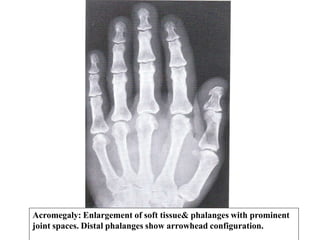

Appendicular Skeleton:

• Hands show characteristics enlargement of bones &

soft tissue with spade like appearance of terminal tufts

or arrow head distal phalanges.

• Widening of the joint spaces (overgrowth of

articular cartilage).

Acromegaly: Enlargement of soft tissue& phalanges with prominent

joint spaces. Distal phalanges show arrowhead configuration.